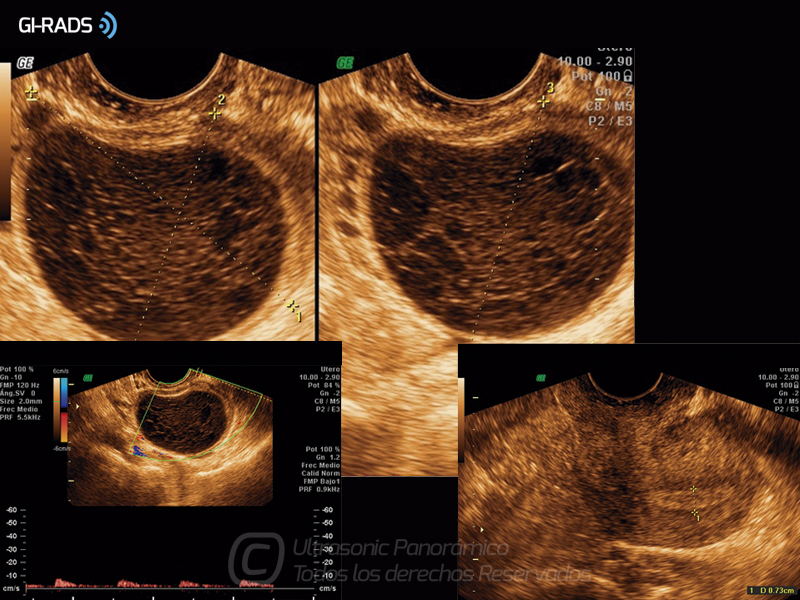

Patologías Benignas – Cuerpo Lúteo Hemorrágico

• Patologías Benignas – Cuerpo Lúteo Hemorrágico